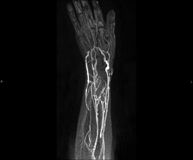

Prova diagnòstica no invasiva que consisteix en l'estudi de l'artèria aorta abdominal per obtenir imatges d'alta definició anatòmica mitjançant l'ús d'un camp electromagnètic i ones de ràdio (amb un emissor i un receptor). És indispensable l'ús de contrast intravenós paramagnètic (Gadolini). No obstant, no utilitza radiació ionitzant. La qualitat de les imatges permet realitzar reconstruccions en 2D i 3D. Està especialment indicada en pacients amb sospita de malaltia vascular de les dues extremitats, en pacients amb malaltia vascular de les dues extremitats com a mapa vascular abans del tractament (percutani o quirúrgic), com a mapa vascular prequirúrgic en pacients amb lesions òssies o musculars que requereixin cirurgia, etc. - Angio-RM Lesión partes blandas

Prueba diagnóstica no invasiva que consiste en el estudio de las arterias de la cintura escapular, brazo, antebrazo y mano obteniendo imágenes de alta definición anatómica mediante el empleo de un campo electromagnético y ondas de radio (con un emisor y un receptor). Es indispensable el uso de contraste intravenoso paramagnético (gadolinio). Sin embargo, no utiliza radiación ionizante. La calidad de las imágenes permite realizar reconstrucciones en 2D y 3D. Está especialmente indicado en aquellos pacientes en los que hay sospecha de enfermedad vascular de ambas extremidades, en pacientes con enfermedad vascular de ambas extremidades como mapa vascular antes del tratamiento (percutáneo o quirúrgico), como mapa vascular pre-quirúrgico en pacientes con lesiones óseas o musculares que requieran cirugía…